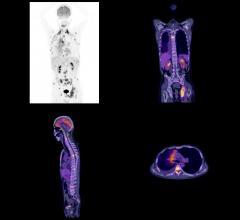

February 29, 2016 — Metastatic prostate cancer, where better therapeutic strategies are desperately needed, appears to ...